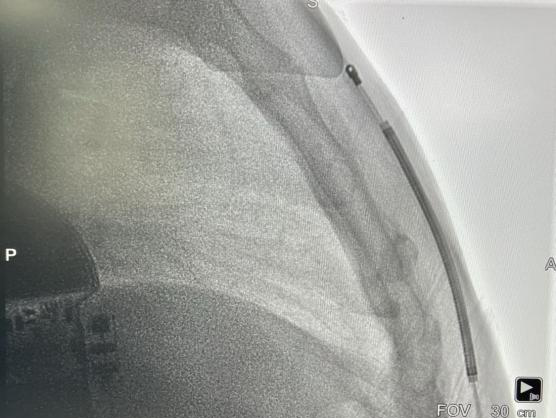

术后影像

手术在全麻醉下进行。常规消毒、铺巾,取左腋中线平等第5-6肋为预定点,切开一约5cm切口,逐层分离至皮下,分离囊袋至背阔肌与前锯肌之间。再次于胸骨柄右缘1cm为预定点,切开一长约3cm切口,逐层分离至深筋膜层,预埋两根缝合线用导引针,于切口间建立隧道,利用隧道针将电极沿皮下置入囊袋。再以切口位置建立隧道,同样以隧道针将导线头端沿深筋膜层,送至胸骨柄上缘(距切口14cm处),于切口处固定电极导线,囊袋处连接脉冲发生器(S-ICD A209),固定脉冲发生器于深筋膜层,排除空气后关闭深筋膜层。进行DFT测试,采用50HZ,200MA交流电方式进行诱颤,SICD正确识别,经首次65J除颤成功,除颤阻抗77欧姆。缝合皮肤,术区纱布覆盖,包扎,弹力绷带加压包扎止血。手术圆满成功,耗时约50分钟,术后第二天患者即可下床活动。